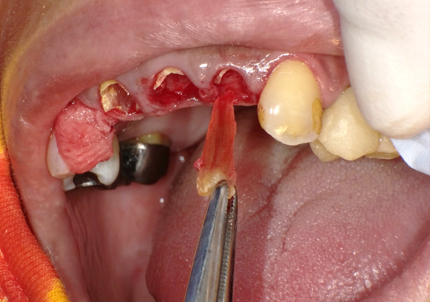

4.左下5番ソケットシールドテクニック

【ソケットシールドテクニックにより保存した歯牙片の内側にインプラントを埋入するCTシミュレーション】

【上記シミュレーションにて作製したガイドを用いたインプラント埋入】

5.インプラント埋入(2021年6月)